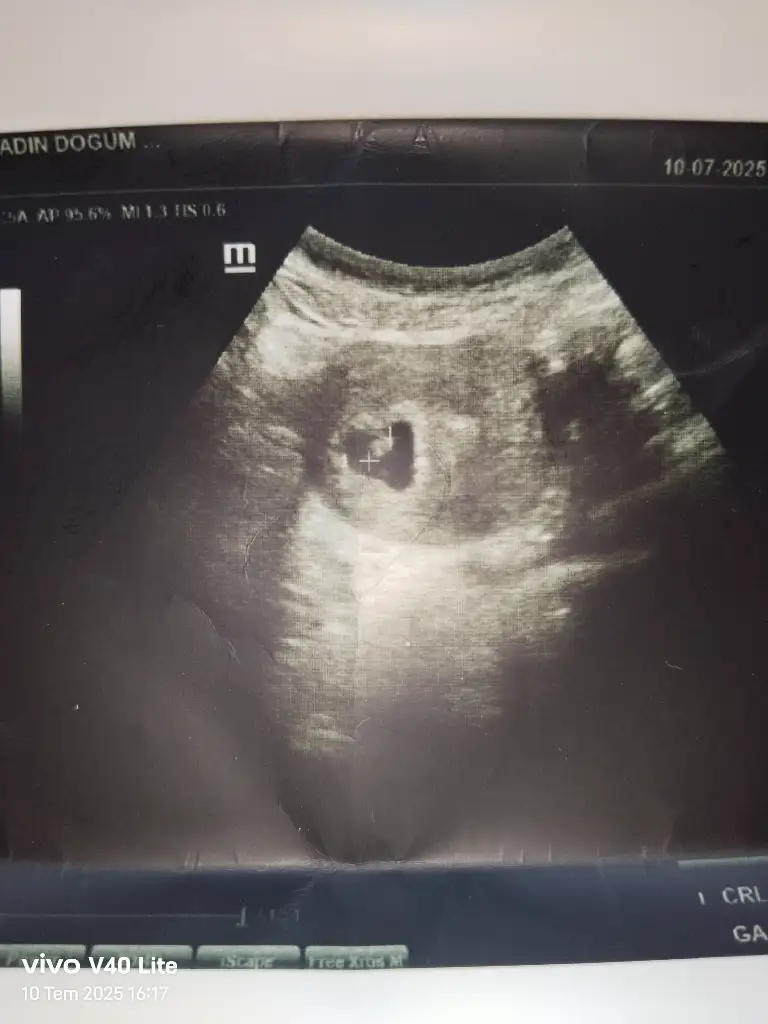

Gözünüz aydın sağlıkla kucağınıza almakta nasip olsunCinsiyet tahmini yapabilden var mı aranızda bugün kalp atışı da duyduk bebişi de gördük 6 hafta 4 günlük

Bence erkek bebek tamamen hissiyatCinsiyet tahmini yapabilden var mı aranızda bugün kalp atışı da duyduk bebişi de gördük 6 hafta 4 günlük

Benimki nedir sizce teşekkür ederim sağolunGözünüz aydın sağlıkla kucağınıza almakta nasip olsunkese yuvarlak ise kız şekilli ve fasulye gibiyse erkek diyorlar cogu kisidede tutmus ama bilemiyorum